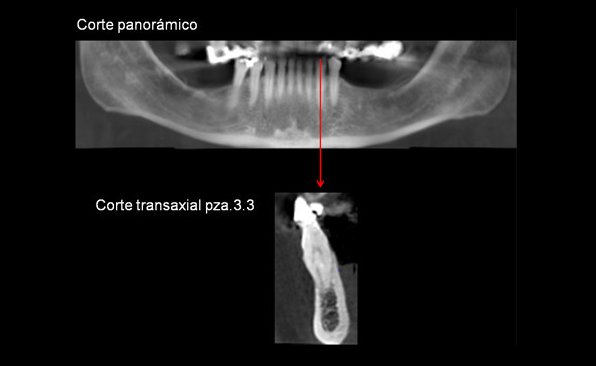

Paciente femenino de 54 años de edad, asintomática, es referida a la consulta para la evaluación con Tomografía volumétrica previa a la colocación de implantes. A la observación de los cortes axiales se evidencian dos raíces en la pieza 3.3, el corte transaxial muestra la bifurcación a nivel del tercio cervical.